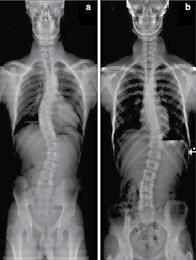

30 콜로라도 타임즈 · 2022년 11월 10일 목요일 · 1052호 교통사고 후유증 / 목 통증 / 목 디스크 / 오십견 / 어깨통증 말초신경장애: 손, 발, 다리의 통증, 저림, 근육약화감, 감각상실 (편)두통 / 불면증 / 어지러움 / 턱관절 장애(TMJ) 척추측만증(Scoliosis) / 척추협착증 / 허리수술 후유증 허리통증 / 허리 디스크 / 관절염 / 좌골신경통 / 고관절, 발목, 손목 통증 ▪ ▪ ▪ ▪ ▪ ▪ ▪ ▪ ▪ 최첨단 목/허리 디스트 치료기기 최신형 디지털 X-ray 시설 Therapeutic Massage ▪초음파, 전기치료 Gonstead Chiropractic 교정치료 치료 진료과목 청소년을 위한 척추교정 프로그램 성장이 빠른 청소년기에 척추가 똑바로 자라야 척추 측만증이 예방됩니다. 성장기의 자녀에게 척추교정으로 바른 자세와 건강한 삶을 선물하세요. 무료 척추검사무료 척추검사 무료 상담무료 상담 무료 상담무료 상담 교통사고 치료 전문 Southern California University of Health Science Doctor of Chiropractic 콜로라도주 척추신경 보드 정회원 캘리포니아주 척추신경과 보드 정회원 National Board 척추신경과 정회원 손석기 D.C. 원장, 척추신경 전문의 chiro1health@gmail.comOpen Hours 월/수/금 9am-6pm 화/목: 2pm-6pm 자동차 보험 건강 보험 상해 보험 교통사고후유증,척추·관절통증,더이상참지마세요!